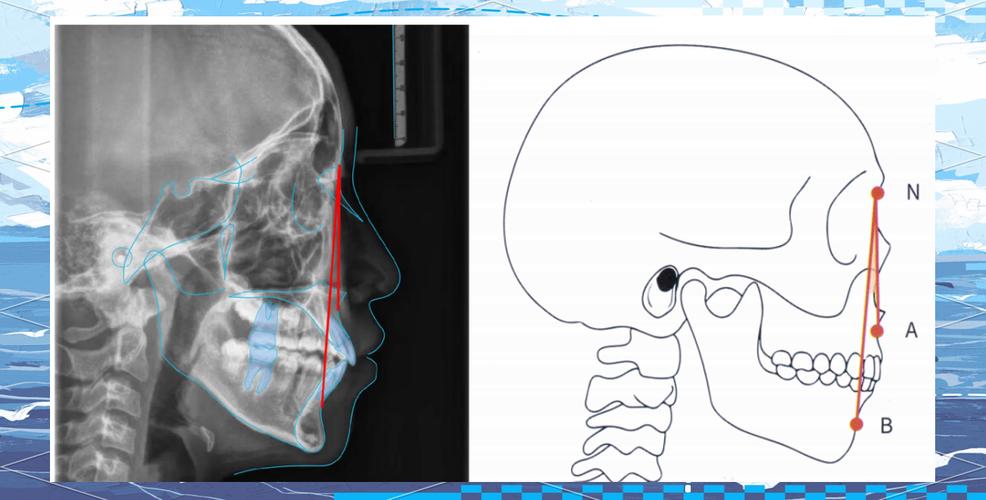

ANB角的测量依赖于头颅侧位片的准确定位与标志点识别,需在头颅侧位片上确定三个核心标志点:鼻根点(N),位于鼻额缝的最前点,是颅底参考平面的起点;上齿槽座点(A),为前鼻棘与上牙槽突缘的交点,代表上颌骨基骨的位置;下齿槽座点(B),为下牙槽突缘与颏前点的交点,代表下颌骨基骨的位置,随后,以蝶鞍中心点(S)与N点连线构成SN平面(颅底参考平面),分别测量NA连线与NB连线相对于SN平面的夹角(即SNA角与SNB角),ANB角则为SNA角与SNB角的差值(ANB角=SNA角-SNB角)。